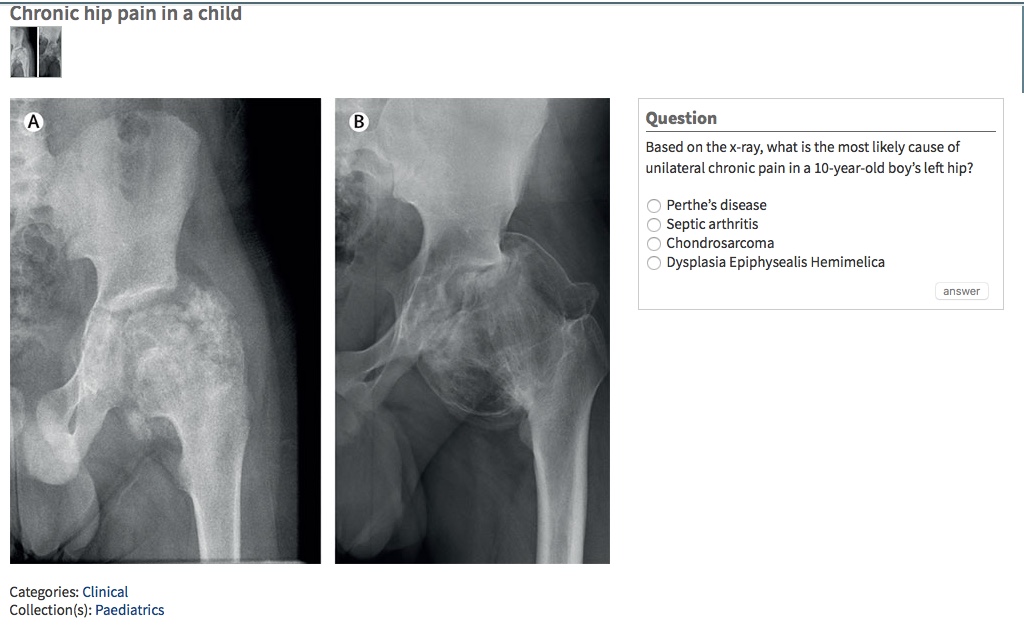

Cue the Jeopardy theme song. “What is….” Click here to answer! #TheLancet #PictureQuiz Share this: Share on X (Opens in new window) X Share on Facebook (Opens in new window) Facebook Like Loading... Published by UBC Abbotsford-Mission Family Practice Residency Program View all posts by UBC Abbotsford-Mission Family Practice Residency Program